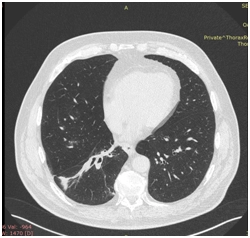

КТ ОГП 06.01.2017. КТ-картина внутрипросветного патологического мягкой плотности компонента (центральный рак?) в промежуточном бронхе правого легкого с ателектазом нижней доли. Лимфаденопатия правого корня, количественная лимфаденопатия средостения.